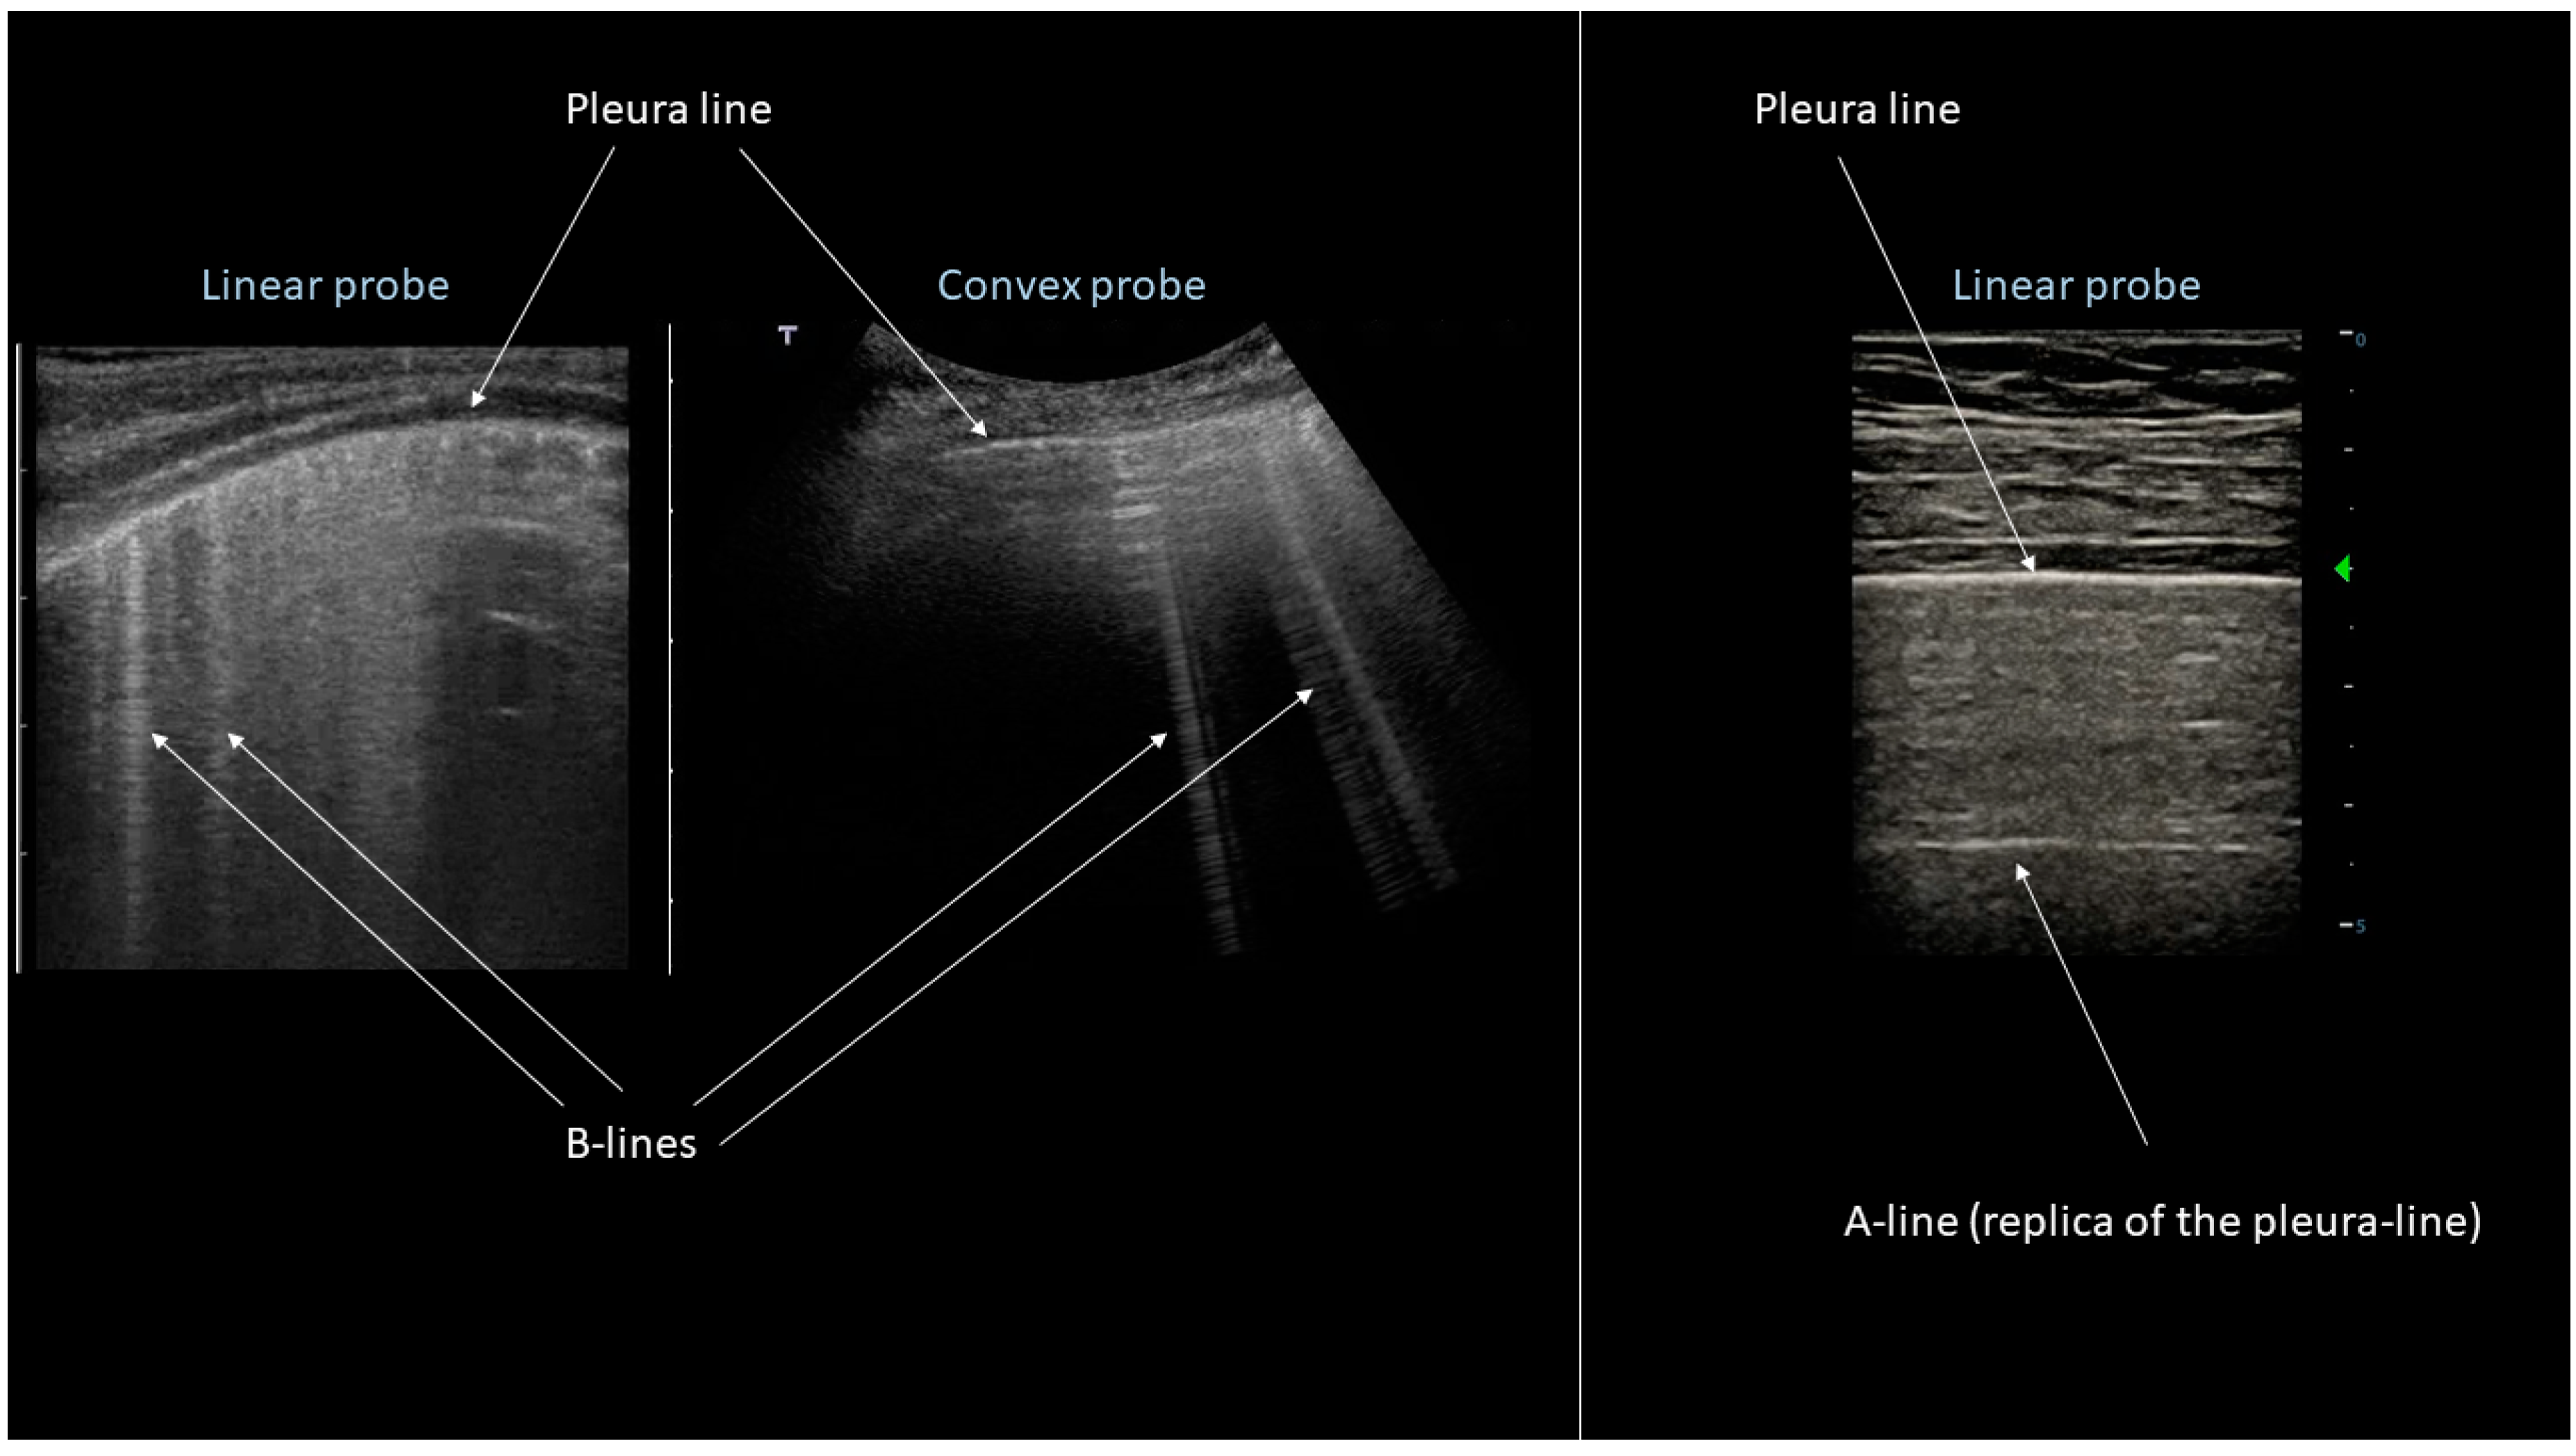

- Avruch, L.; Cooperberg, P.L. The Ring-Down Artifact. J. Ultrasound Med. 1985, 4, 21–28. [Google Scholar] [CrossRef] [PubMed]

- Lichtenstein, D.A.; Mézière, G.; Biderman, P.; Gepner, A.; Barré, O. The Comet-tail Artifact: An Ultrasound Sign of Alveolar-Interstitial Syndrome. Am. J. Respir. Crit. Care Med. 1997, 156, 1640–1646. [Google Scholar] [CrossRef] [PubMed]

- Lichtenstein, D.A.; Mézière, G. A lung ultrasound sign allowing bedside distinction between pulmonary edema and COPD: The comet-tail artifact. Intensive Care Med. 1998, 24, 1331–1334. [Google Scholar] [CrossRef] [PubMed]

- Soldati, G.; Giunta, V.; SHER, S.; Melosi, F.; Dini, C. Synthetic Comets: A new Look at Lung Sonography. Ultrasound Med. Biol. 2011, 37, 1762–1770. [Google Scholar] [CrossRef] [PubMed]

- Jambrik, Z.; Monti, S.; Coppola, V.; Agricola, E.; Mottola, G.; Miniati, M.; Picano, E. Usefulness of ultrasound lung comets as non-radiologic sign of extravascular lung water. Am. J. Cardiol. 2004, 93, 1265–1270. [Google Scholar] [CrossRef] [PubMed]

- Volpicelli, G.; Elbarbary, M.; Blaivas, M.; Lichtenstein, D.A.; Mathis, G.; Kirkpatrick, A.W.; Melniker, L.; Gargani, L.; Noble, V.E.; Via, G.; et al. International Liaison Committee on Lung Ultrasound (ILC-LUS) for the International Consensus Conference on Lung Ultrasound (ICC-LUS). International evidence-based recommendations for point-of-care lung ultrasound. Intensive Care Med. 2012, 38, 577–591. [Google Scholar] [CrossRef]

- Lichtenstein, D.A. Lung ultrasound in the critically ill. Ann. Intensive Care 2014, 4, 1. [Google Scholar] [CrossRef]

- Anderson, K.; Fields, J.M.; Panebianco, N.; Jeng, K.; Marin, J.; Dean, A.J. Inter-Rater Reliability of Quantifying Pleural B-Lines Using Multiple Counting Methods. J. Ultrasound Med. 2013, 32, 115–120. [Google Scholar] [CrossRef]

- Soldati, G.; Demi, M.; Inchingolo, R.; Smargiassi, A.; Demi, L. On the physical basis of pulmonary sonographic interstitial syndrome. J. Ultrasound Med. 2016, 35, 2075–2086. [Google Scholar] [CrossRef] [PubMed]

- Soldati, G.; Demi, M.; Smargiassi, A.; Inchingolo, R.; Demi, L. The role of ultrasound lung artefacts in thediagnosis of respiratory diseases. Expert Rev. Respir. Med. 2019, 13, 162–172. [Google Scholar] [CrossRef] [PubMed]